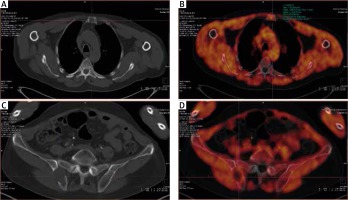

Fig. 1

Patient no. 12, newly diagnosed multiple myeloma before the treatment. A) Computed tomography – lytic lesion localised in the sternum. B) The same lesion on 18F-FET PET/CT fusion image with high FET uptake (converted to black and white). C) Computed tomography – lytic lesion localised in the right iliac crest. D) 18F-FET PET/CT fusion image with high FET uptake in iliac crest